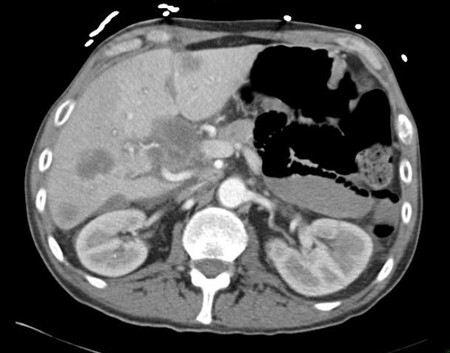

CT abdomen with intravenous contrast, revealing numerous enhancing liver lesions in both hepatic lobes. Percutaneous biopsy of a right lobe lesion revealed adenocarcinoma

From the personal collection of Dr D. Cosgrove